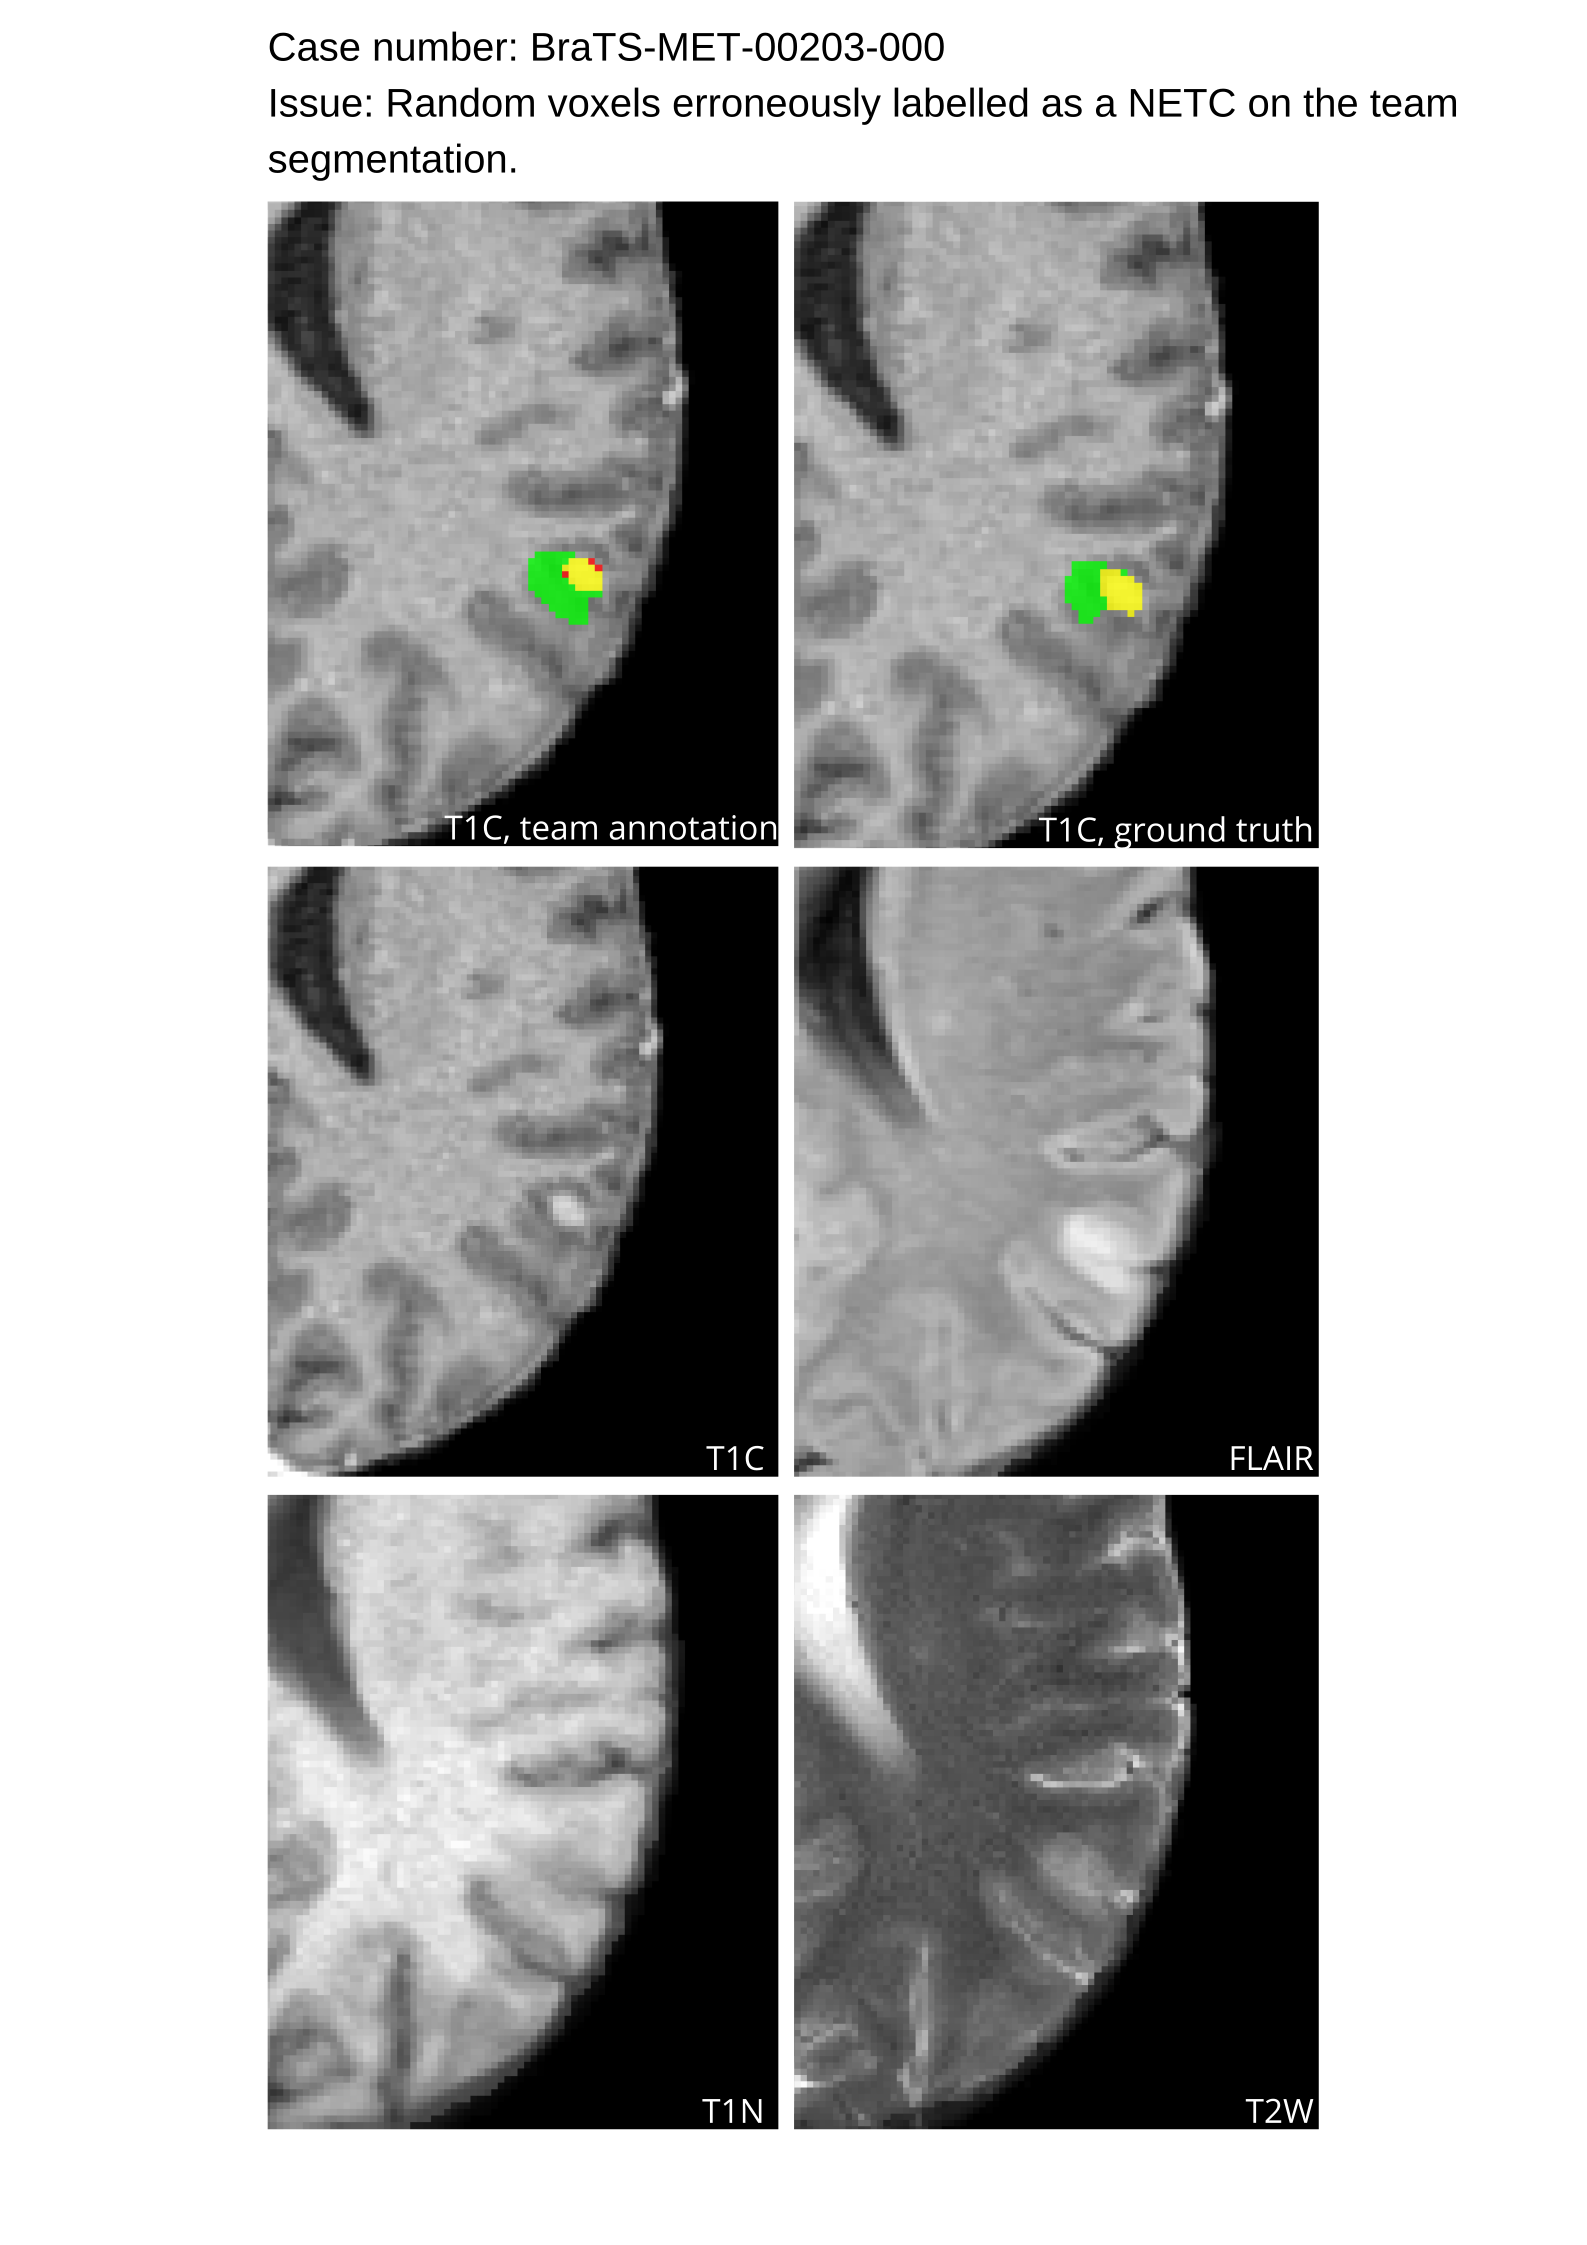

Approvers reviewed the volunteer annotations and either approved the case or returned it to students for re-annotation. Additionally, a QC process was implemented, which included removing all random voxels and any voxels outside the brain mask, ensuring all images had the same parameters (space, orientation, and origin) as the SRI24 atlas, and verifying the presence of all segmentations and segmentation masks are in the folder with original NIfTI images.

Acknowledging the variability in lesion significance arising due to human error, a volumetric threshold of 2 voxels (2 mm3superscriptmm3\text{mm}^{3}mm start_POSTSUPERSCRIPT 3 end_POSTSUPERSCRIPT) was established by an expert panel of clinical radiologists, below which the models’ performance on deemed ”small/false” lesions is not considered in the evaluation. This approach was primarily adopted to ensure that participants were not unfairly penalized for stray voxels in the GT labels, which may result from human error, or for small lesions unrelated to the pathology central to the challenge. The expert panel of clinical radiologists also determined the dilation factor, which was uniformly applied for combining lesions in the GT masks. A dilation factor of 1 voxel in 3D space was chosen because BMs can be small, and it is important to avoid combining these small BMs.

Table 4 provides the relative ranking for each team. Team NVAUTO ranked first in the challenge, with an average rank across subjects of 7.9 and a PatientWise mean of 0.38. Team SY placed second with a PatientWise mean of 0.41 across all patients. The supplementary material depicts the pitfall cases with figures illustrating the false positives or missed lesions.